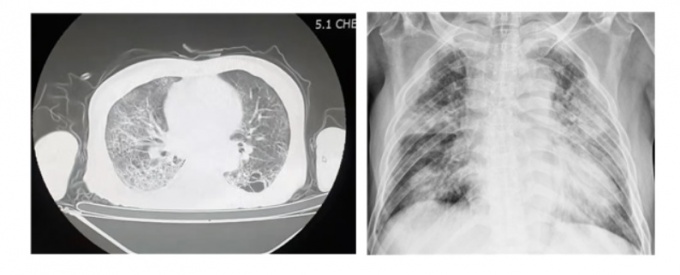

이어 “청도대남병원은 사진으로 보이는 것처럼 병상에 베드도 없이 바닥에 메트리스 깔고 생활하는데 이러한 시설의 낙후됨과 열악함이 코로나19 전파에 더욱 힘을 싣어줬을 수 있다”라고 덧붙였다.

해당 7명은 청도 대남병원 폐쇄병동 장기입원 환자로 폐 관련 기저질환을 앓고 있었으며, 오랜 투병으로 건강이 불량한 상태에서 코로나19로 인한 폐렴이 급속히 진행돼 사망했다.

이 과장은 “정신병동은 환자 특성상 창문을 못 열어 자연환기가 어렵고 환자들은 표현을 잘 안 해 조기진료가 어렵다”며 “또한 병원에서 10~20년 동안 입원생활을 지속한 환자들은 면역력이 굉장히 저하돼있는 상태라 한번 전파되면 예후가 좋지 않다”고 말했다.